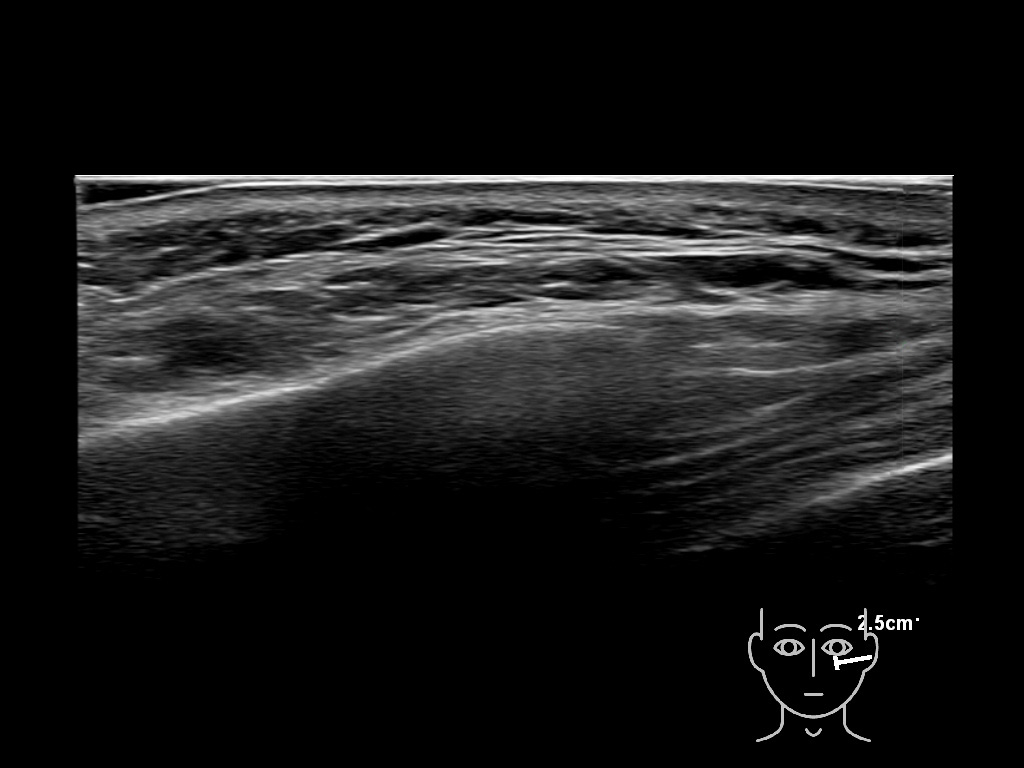

Filler behavior - Temple zygoma US

Study the first image to recognize the different layers. If you are sure about the layers, swipe to the second image to view the answer (if applicable).